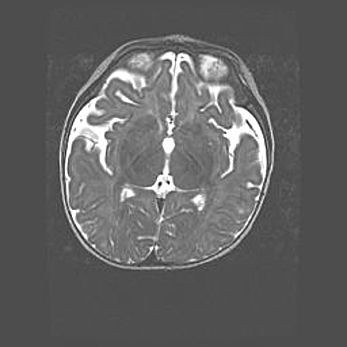

Церебральная ишемия II.

Возраст: 7 дней

Вес: 3350 г

Пол: женский

Окружность головы: 35 см

Срок гестации: 39 недель

Ишемия головного мозга – это состояние, которое развивается в ответ на кислородное голодание вследствие недостаточного мозгового кровообращения. У новорожденных она является следствием дефицита кислорода, что ведет к метаболическим расстройствам различной степени тяжести в тканях головного мозга, в том числе к развитию коагуляционных некрозов и гибели нейронов.